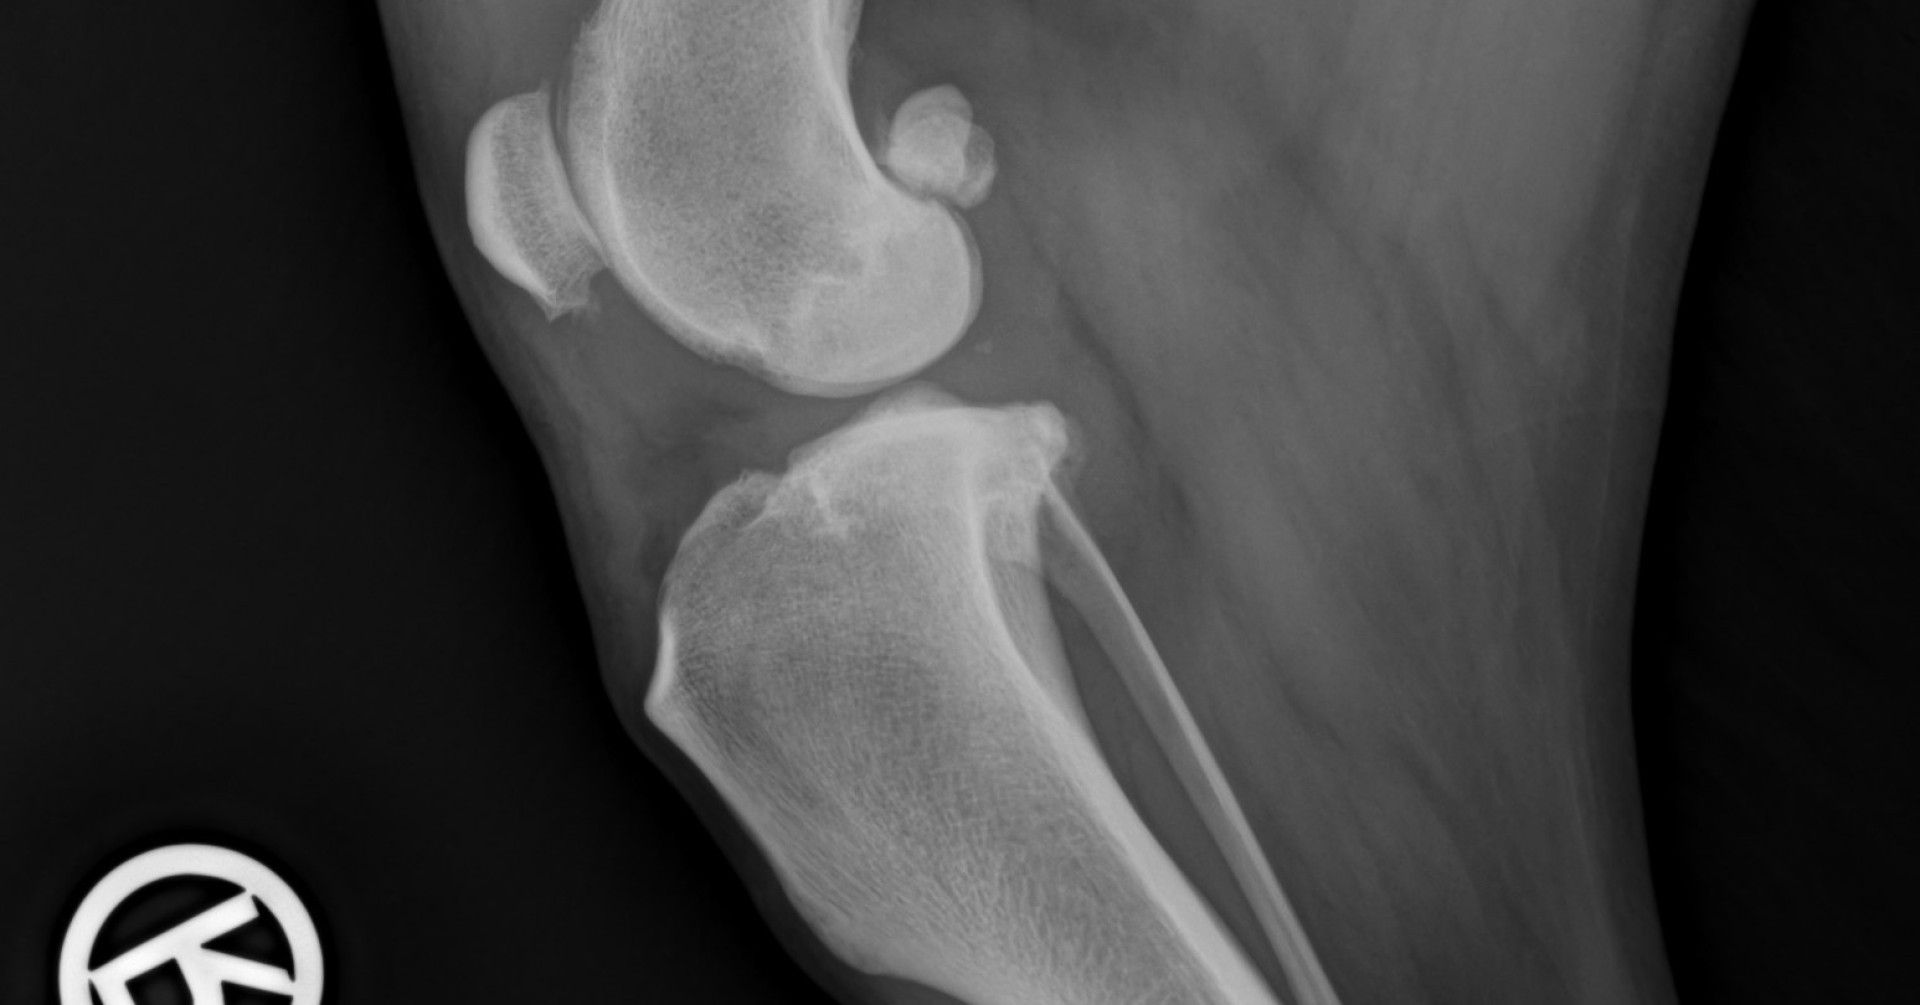

Im Kniegelenk befinden sich zwei Kreuzbänder, die das Gelenk stabilisieren. Reißt eines davon – meist das vordere Kreuzband –, führt das zu einer plötzlichen oder schleichenden Lahmheit. Typisch: Der Hund schont das betroffene Bein, setzt es nur kurz auf oder entlastet es vollständig.

In den meisten Fällen ist ein chirurgischer Eingriff notwendig, um die Stabilität des Gelenks wiederherzustellen. Je nach Größe und Aktivitätsniveau des Hundes kommen unterschiedliche OP-Methoden zum Einsatz. Eine konservative Behandlung ist nur in seltenen Fällen sinnvoll.